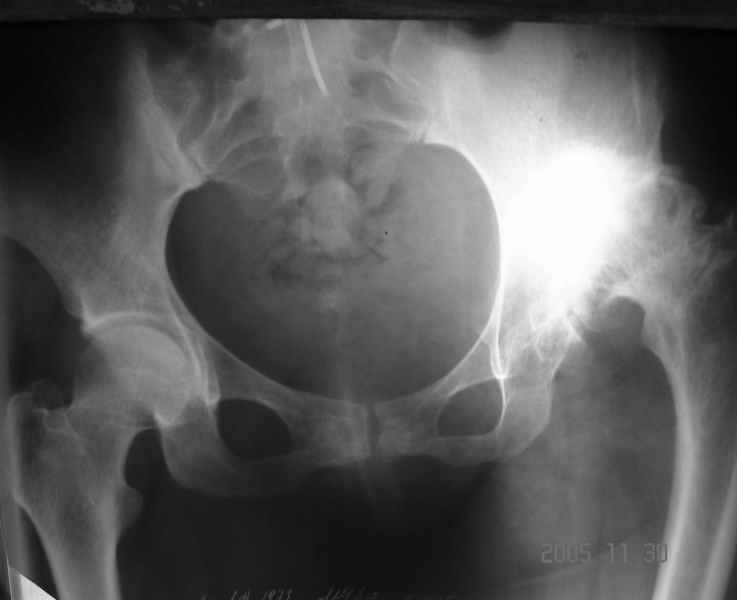

Уважаемые коллеги, прошу дать совет по данному случаю. Пациентка 32 лет с диспластическим левосторонним коксартрозом 3 ст. Из анамнеза - в детстве операции по поводу врожденного вывиха левого бедра (остеотомия таза по Хиари и остеотомия проксимального отдела бедра, аппаратное удлинение голени) В настоящее время беспокоят боли в левом тазобедренном суставе, ограничения движения (сгибание 60 гр, отведение 20 гр, общ ротация 30 гр); укорочение левой н/конечности на 5 см. Пациентка ставит задачу о полноценности тазобедренного сустава и коррекции длины нижней конечности. Р-гр прилагаются. Какой тип эндопротеза оптимален в данном случае? Как проводить коррекцию укорочения? (аппаратное удлинение голени после протезирования?)Буду весьма благодарен за помощь.

Другой и самый сложный вопрос - расположение и фиксация вертлужного компонента. На мой взгляд, оптимальное решение - расположение чашки в анатомическом положении с компенсацией недопокрытия за счет аутокостной пластики (из удаленной головки). Если Вы подниметесь выше (более 2,5-3 см), то велика опасность проваливания в полость малого таза, т.к. предсказать истинную анатомию после перенесенной остеотомии таза про Хиари крайне сложно. Как показывает опыт, после такой остеотомии лучше не верить картинке стандартной Р-граммы, а ориентироваться на анатомическое положение фигуры слезы. Хорошим решением была бы КТ.

Уважаемый Алексей! На наш взгляд пациентке необходимо выполнить бесцементное эндопротезирование. Особое внимание уделить формированию имплантационного ложа чашки протеза -симметрично контрлатеральному суставу. То есть центрировать фрезу в истинную acetabulum, а не во впадину неоартроза. Причем использование небольшого размера (44-46 мм) впадины протеза позволит её надежно закрепить в тазовой кости без какой-либо костной пластики. Если будет выраженный пороз тазовой кости, то следует предусмотреть впадину с цементной фиксацией. Укорочение нивелируется после протезирования. Дополнительно ничего удлинять не надо. Но имеется вальгус коленного сустава, который возможно придется устранять корригирующей надмыщелковой остеотомией.